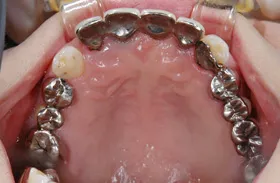

■治療前:奥歯が無いため噛み合わせが深く下の歯が全く見えない

噛み合わせが低いため全体的に歯が削れている

■治療後:下顎 左下5・6番、右下4・6番にインプラント治療

その他の歯に補綴治療をしたことにより、奥歯もしっかりと咬むことができ、奥歯ができたことにより噛み合わせも上がって下の歯も見えるようになり、審美的にも改善された

| 主訴 | 歯科治療をしても歯がすぐに欠けてしまう 奥歯が無いため、奥歯で咬めない |

|---|---|

| 治療方法 | インプラント治療 + 補綴治療 |

| 治療期間 | 約1年 |

| 通院回数等 | 約20回 |

| 費用 | 約250万円(税込) |

| リスク・副作用 | 術後の腫れ・痛み |